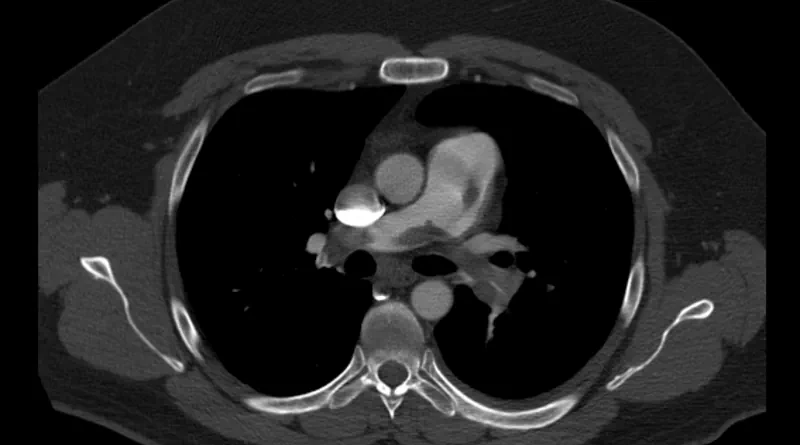

Blood Clot Diagnosis with CT or MRI

We usually diagnose blood clots in the lungs or in the abdominal veins with CT. Sometimes, we identify clots in the abdominal or pelvic veins with MRI. A special type of MRI called MRV is useful to diagnose iliac vein compression (May-Thurner Syndrome).